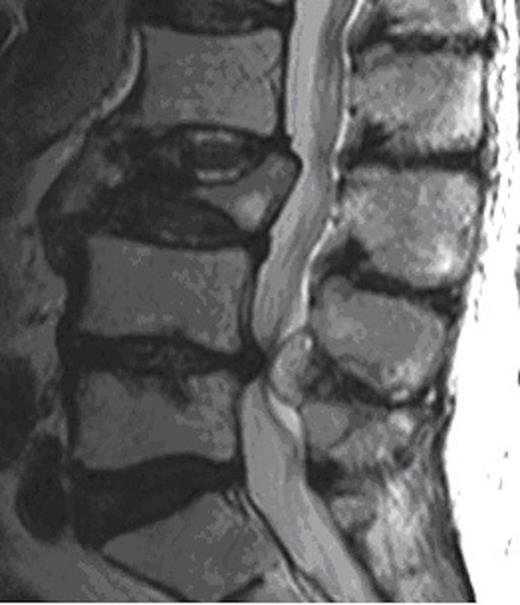

MRI of the whole spine revealed that he had multiple metastatic deposits throughout his spine with complete collapse of L3 vertebral body but intact disc space. Significant spinal canal stenosis at L4/5 level was seen due to a degenerative posterior disc bulge as well as a 2 x 1 x 1 cm size well capsulated, well defined lesion seeming to arise fromthe ligamentum flavum contributing to the canal narrowing.The appearances were thought to be either due to underlying haematoma from ligamentum flavum or a haemorrhagic synovial cyst. Significant cauda equina compression was noted.